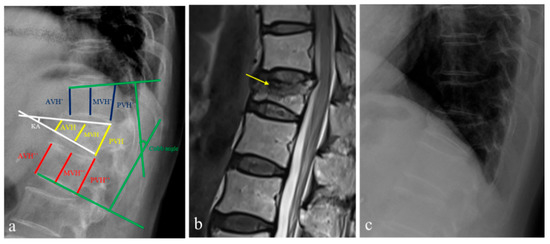

Radiological Factors Associated with Bisphosphonate Treatment Failure and Their Impact on Fracture Healing in Postmenopausal Women with Osteoporotic Vertebral Fractures

(1) Background: Bisphosphonate treatment failure is one of the most difficult clinical problems for patients with osteoporosis. This study aimed to analyze the incidence of bisphosphonate treatment failure, associated radiological factors, and effect of fracture healing in postmenopausal women with osteoporotic vertebral fractures [...] Read more.

(1) Background: Bisphosphonate treatment failure is one of the most difficult clinical problems for patients with osteoporosis. This study aimed to analyze the incidence of bisphosphonate treatment failure, associated radiological factors, and effect of fracture healing in postmenopausal women with osteoporotic vertebral fractures (OVFs). (2) Methods: A total of 300 postmenopausal patients with OVFs who were prescribed bisphosphonate were retrospectively analyzed and divided into two groups according to the treatment response: response (n = 116) and non-response (n = 184) groups. The radiological factors and the morphological patterns of OVFs were included in this study. (3) Results: The initial BMD values of the spine and femur in the non-response group were significantly lower than those in the response group (all Ps < 0.001). The initial BMD value of the spine (odd ratio = 1.962) and the fracture risk assessment tool (FRAX) hip (odd ratio = 1.32) showed statistical significance in logistic regression analysis, respectively (all Ps < 0.001). (4) Conclusions: The bisphosphonate non-responder group showed a greater decrease in BMD over time than the responder group. The initial BMD value of the spine and the FRAX hip could be considered radiological factors influencing bisphosphonate non-response in the postmenopausal patients with OVFs. The failure of bisphosphonate treatment for osteoporosis has a possible negative on the fracture healing process in OVFs. Full article